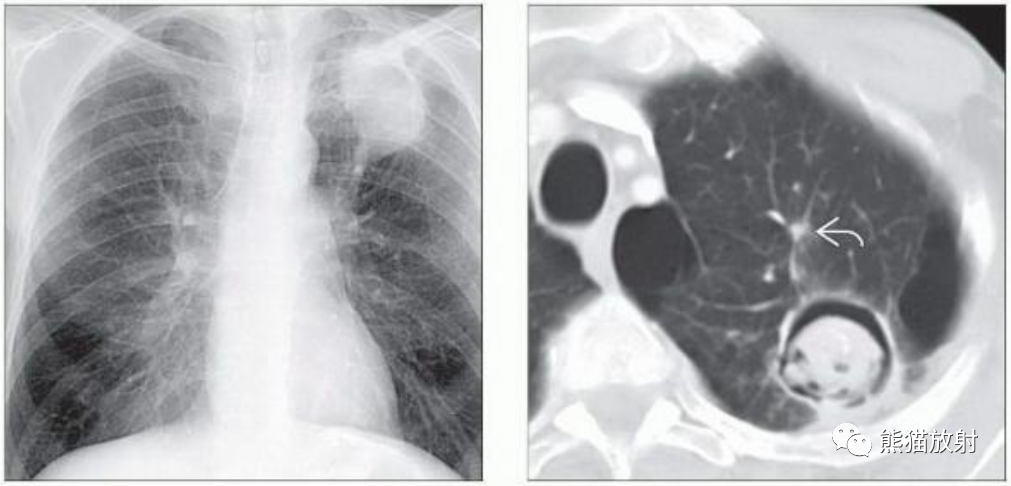

(左) 50岁男性,HIV感染并大咯血。胸片显示左肺上叶肿块,边缘不规则,其内局部透亮度增高,提示空气新月征。

(右) 同一患者,轴位CT显示厚壁空洞病变,中央见不均匀软组织密度灶,周围见磨玻璃影及小结节。术后诊断为侵袭性曲霉菌病。